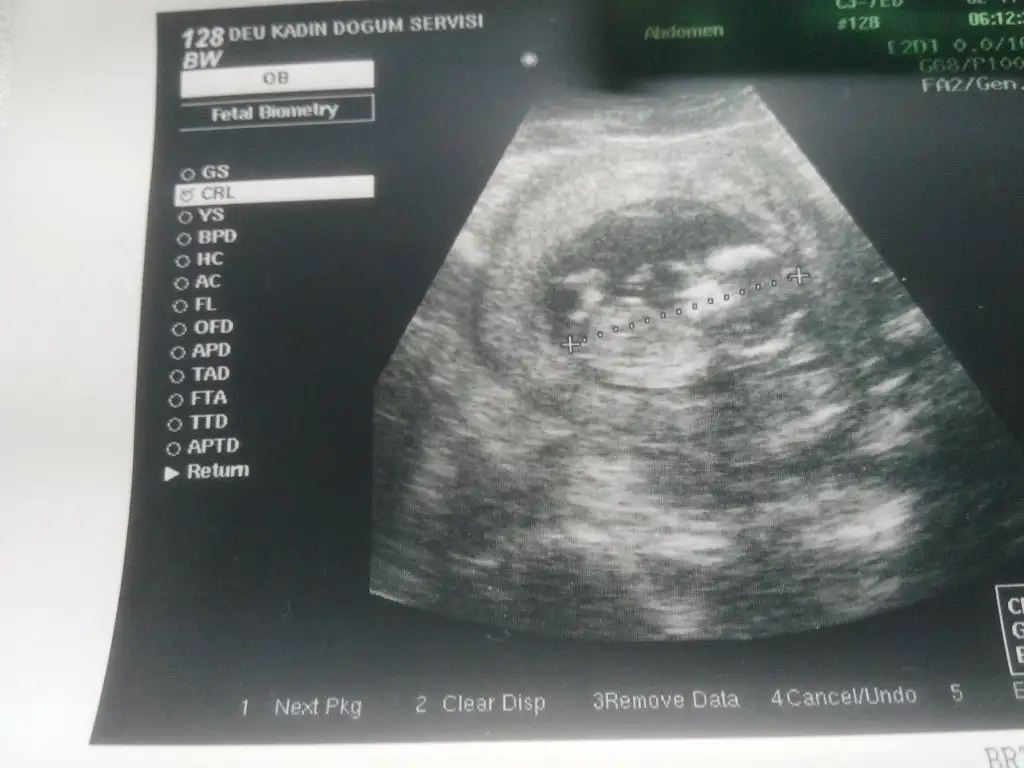

Oğlana benzettim ben o çıkıntıyı görünce :)Kızlar benimki ney sizce. bi kızım var erkek istiyodum.doktor duruşu kıza benziyor ama bişey diyemem dedi.sizce nedir acaba 12 haftalık gebeyim.

canım çok net değil nubu ama bana kız gibi geldi..O Çıkıntı nub değil kızlar bacak :))) tam yan değil bebeiş arkasını dönmüş saklamış...Kızlar benimki ney sizce. bi kızım var erkek istiyodum.doktor duruşu kıza benziyor ama bişey diyemem dedi.sizce nedir acaba 12 haftalık gebeyim.

nub net değil bişey söylemek çok zor canım...

Evet kızlarr bana da yorum hadi bakalımbenimde var bir kaç tahminim ama doktor söylemedi tahmini olduğu halde Eki Görüntüle 1421184